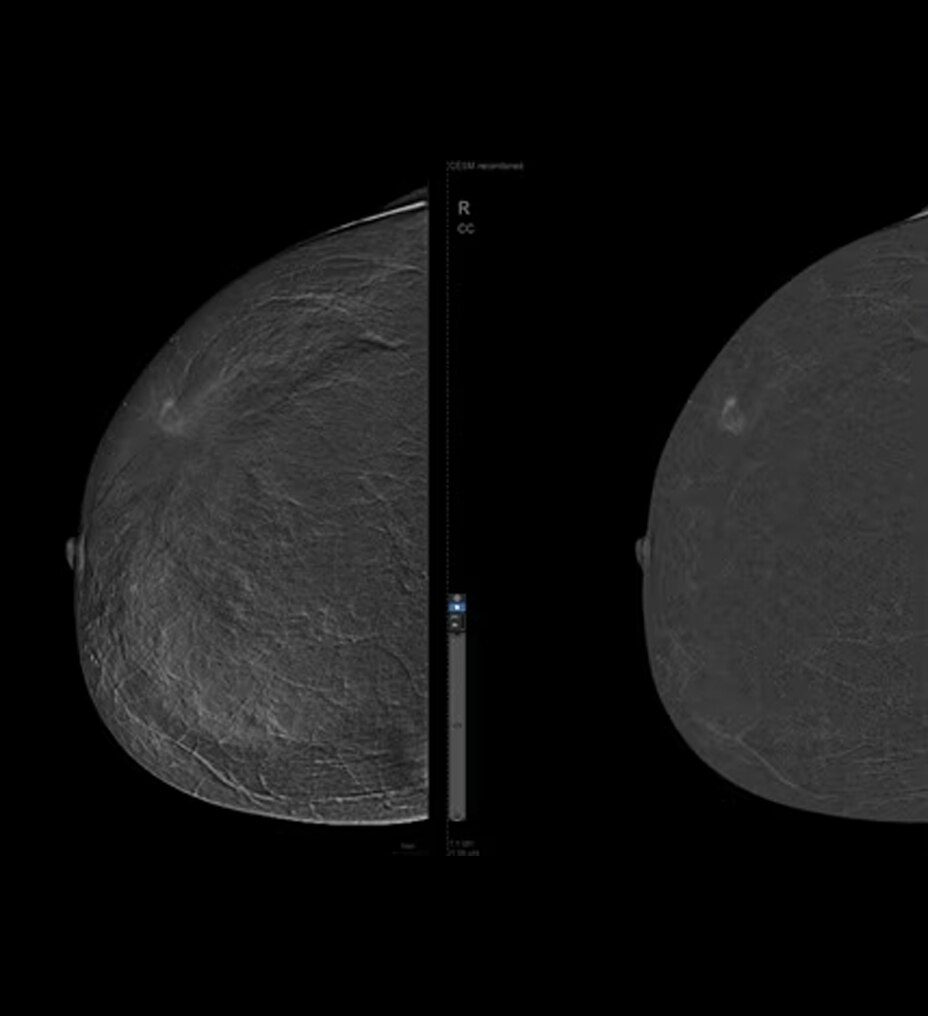

Alimentado por la tecnología SignalMax™, para que no tenga que comprometer la calidad de la imagen para la portabilidad